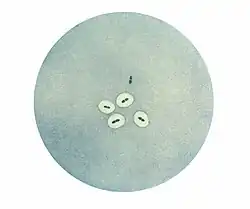

![]() Obraz pneumokoków w skaningowym mikroskopie elektronowym | |

Dwoinka zapalenia płuc ma kształt kulisty lub zbliżony do kuli, średnicę około 1μm i jest zaliczana do ziarniaków. Bakterie układają się zazwyczaj w pary, a kolonie mogą przyjmować obraz łańcuszków różnej długości.